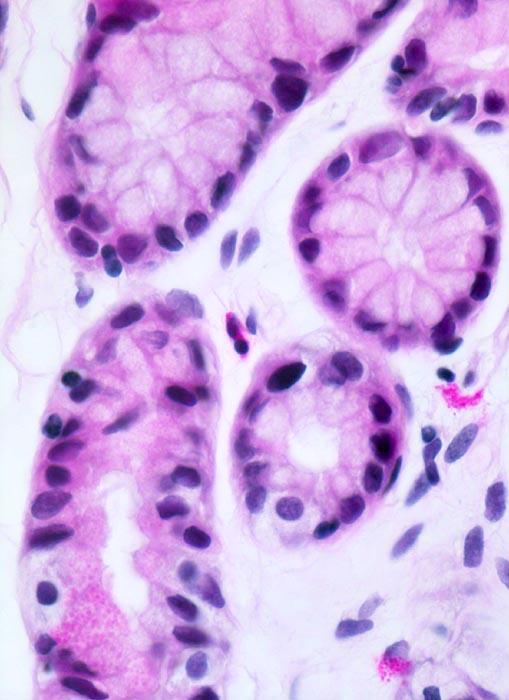

• Intestinale Metaplasie der Antrumschleimhaut: Basophile (bläuliche) Drüsenschläuche mit Becherzellen sowie einzelnen Paneth'schen Körnerzellen mit rot granuliertem Zytoplasma im untersten Schleimhautfragment. Die metaplastische Schleimhaut erinnert stark an Kolonschleimhaut.

Das Unterrichtspräparat zeigt eine Helicobacter-Gastritis mit intestinaler Metaplasie. Histologisch ist die Typ B Gastritis charakterisiert durch eine chronische (Plasmazellen und Lymphozyten) und aktive (neutrophile Granulozyten) Entzündung. Das Ausmass der chronischen Entzündung und die Entzündungsaktivität werden gemäss Sydney Klassifikation in drei Schweregrade unterteilt (z.B. mässiggradige chronische, stark aktive Gastritis). Fakultativ können Lymphfollikel, eine intestinale Metaplasie mit/ohne Dysplasie und/oder Drüsenatrophie hinzukommen. Die Erreger (Helicobacter pylori) kolonisieren den protektiven Schleimfilm auf der Magenmukosa (> 3330) (> 9968) und sind dort mittels Spezialfärbung (Giemsa C) mikroskopisch nachweisbar. Unmittelbar im Bereich der intestinalen Metaplasie sind aufgrund des veränderten Milieus meist keine Bakterien nachweisbar. Unter Einnahme von Säurehemmern oder Antibiotika verringert sich die Sensitivität des Bakteriennachweises in der Biopsie aufgrund der schnellen Reduktion der Bakterienanzahl ebenfalls. Nach erfolgreicher Eradikation verschwindet in der Regel die aktive Entzündung innert Wochen. Chronische Entzündung und Lymphfollikel bleiben jedoch länger nachweisbar und geben einen Hinweis auf eine abgelaufene Helicobactergastritis.

• Schwere chronische (dichtes lymphoplasmazelluläres Entzündungsinfiltrat in der Lamina propria), stark aktive (neutrophile Granulozyten in der Lamina propria und im Epithel mit Ausbildung von Mikroabszessen) Gastritis.